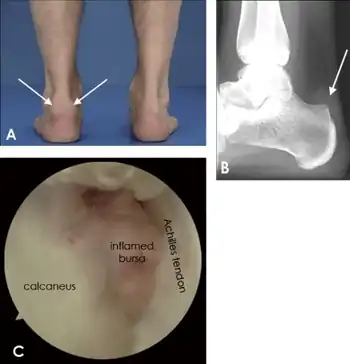

a,b)Individual with retrocalcaneal bursitis c) endoscopic view of retrocalcaneal bursitis.

Retrocalcaneal bursitis is an inflammation of the bursa located between the calcaneus and the anterior surface of the Achilles tendon.[1] It commonly occurs in association with rheumatoid arthritis, spondyloarthropathies, gout, and trauma.

The pain is usually on the back of the heel and swelling appears on lateral or medial side of the tendon.